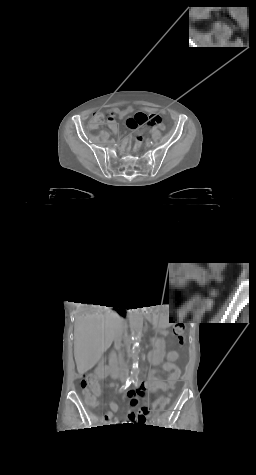

(a)

Refer to caption

(b)

(c)

(d)

Figure 3: (a) Axial (top) and coronal (bottom) slices of abdominal CT, HU range=(-400, 400) and (-150, 250) for ROI, (b) U-net (c) \partialU-net, (d) LIRE++

We perform extensive evaluation of LIRE++ and the baselines using image quality metrics such as PSNR and SSIM, which are computed for attenuation values, as well as MAE in Hounsfield Units due its importance for radiotherapy applications.

In Table 1 we report these metrics on the thorax & pelvic test set, and the corresponding box plots are provided in Figure 1. All metrics are computed for the full field of view region, i.e., the voxels which are present in at least half of the projections, which coincides with the field of view given by FDK and TV methods. Table 1 also contains mean total inference times per volume on NVIDIA A100 accelerator and the parameter counts, where in case of FDK and TV the parameter count of scatter pre-correction U-net is provided. In case of TV reconstruction, high inference time is partially due to multiple CPU-GPU memory transfers in ODL. Examples of thorax image slices of a ground truth image and the corresponding reconstructions from baselines and LIRE++ are presented in Fig. 2. Similarly, pelvic & abdominal image slices are presented in Fig. 3. The image samples demonstrate particularly well that LIRE++ is superior in reproduction of these soft tissue details which appear blurred in the baselines. Field-of-view in the reconstructions given by LIRE++ and \partialU-net is increased since the training loss is optimized over all voxels which are present in at least one projection. Extended FoV reconstruction quality for the voxels which are observed in at least one projection, but less than half of all projections, is slightly higher in LIRE++ reconstructions compared to \partialU-Net by appoximately 1 dB higher PSNR.